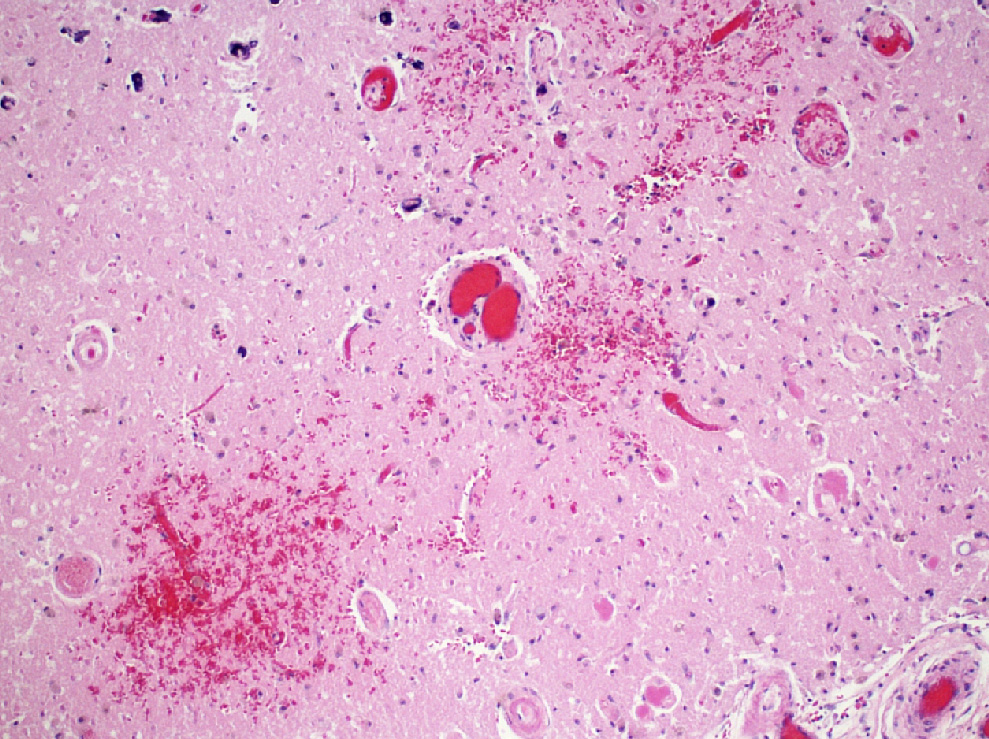

Microscopic (histologic) description

- Acute infarct (1 - 4 days) (Histopathology 2011;58:333)

- Neuronal changes: hypereosinophilic perikaryon (red dead neurons), cell body shrinkage, pyknosis (i.e., nuclear hyperchromasia), loss of demarcation of the nuclear features in later phases

- Neurons are more susceptible to ischemia than glia

- Neuropil vacuolation (i.e., tissue edema)

- May have some neutrophilic infiltrate

- Pannecrosis: all cell populations (i.e., neurons, glia, blood vessels) are necrotic; dead cells remain visible as hypereosinophilic structures that preserve the cell and nuclear outlines (pale neurons or "ghosts")

- Laminar necrosis

- Occurs due to variable susceptibility to hypoxia among the cortical histological layers

- In the mature brain, the most vulnerable neurons are located in cortical layers III, V, VI, Purkinje cells in the cerebellum and pyramidal cells of CA1 field in the hippocampus proper

- Geographic necrosis: liquefied necrotic tissue is well demarcated from the adjacent viable tissue

- Neuronal changes: hypereosinophilic perikaryon (red dead neurons), cell body shrinkage, pyknosis (i.e., nuclear hyperchromasia), loss of demarcation of the nuclear features in later phases

- Subacute (5 - 14 days)

- Dense macrophage infiltration and scattered siderophages

- Variable neutrophilic infiltration

- Peripheral reactive astrocytosis and microglial activation (i.e., rod shaped microglia)

- Hypereosinophilic neurons are still present in gray matter

- Neovascularization of necrotic tissue and reactive endothelial cells

Microscopic (histologic) images